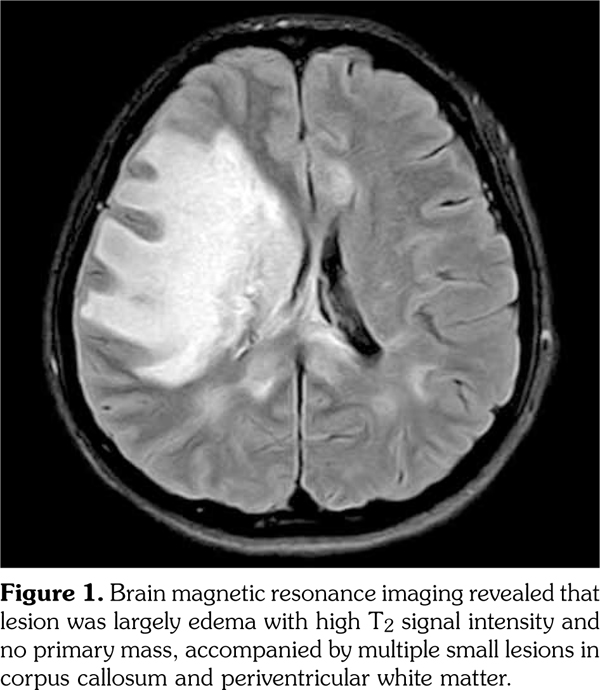

A 43-year-old female patient presented with acute-onset fever, headache, dysarthria, amnesia, left-side weakness, and dysesthesia. Initial brain computed tomography scans showed a 7 cm, mass-like lesion in the right frontoparietal region, suggesting a brain tumor. However, brain magnetic resonance imaging (MRI) revealed that

(a) the lesion was largely edema with high T2 signal intensity and no primary mass, accompanied by multiple small lesions in the corpus callosum and periventricular white matter (Figure 1). The cerebrospinal fluid profile showed the following: white blood count, 16/mm(3) and protein, 55 mg/dL. Considering the possibility of encephalitis, empirical antibiotics and acyclovir were administrated, but no improvements in her symptoms or MRI were observed. Under suspicion of tumefactive multiple sclerosis and other demyelinating diseases, intravenous steroid pulse (methylprednisolone 1 g) therapy for five days and subsequent high-dose prednisolone was administered. The patient recovered enough to walk and only a tingling discomfort remained in the left hand. She was referred to a rheumatologist to screen for underlying autoimmune diseases. She had complained of dry mouth for 10 years, but denied having dry eyes. Blood tests showed the following: positive for antinuclear antibody 1:320 (speckled pattern) and anti-SSA/Ro, and negative for anti-SSB/La, anti-double-stranded deoxyribonucleic acid, rheumatoid factor, and anti-phospholipid antibodies, with normal C3/C4 levels. Salivary scintigraphy showed decreased uptake in the submandibular and parotid glands (Figure 2a), and examinations for dry eyes were positive. A minor salivary gland biopsy showed lymphoplasmacytic infiltration with a focus score >2 (Figure 2b). Therefore, she was diagnosed as having pSS with CNS involvement in the form of tumefactive encephalitis. Monthly intravenous cyclophosphamide therapy was started and glucocorticoids were tapered slowly. A written informed consent was obtained from the patient.